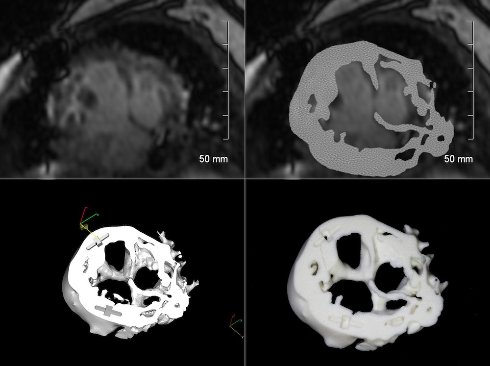

Напечатать модель сердца ребёнка несложно. Нужен всего лишь массив данных, полученный при помощи магнитно-резонансной томографии, а также специальный софт для 3D-принтера, который способен преобразовать исходные данные в полноценный трёхмерный макет, который врач сможет тщательно изучить. Именно благодаря этим моделям хирурги способны принять гораздо более взвешенные решения, способные продлить, а то и спасти жизни множества детей.